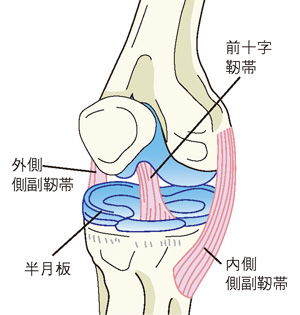

そのほかには、膝の靭帯や半月板損傷といった若い頃のスポーツ外傷に由来する痛みや関節リウマチ、大腿骨内顆骨壊死(だいたいこつないかこつえし)も考えられます。